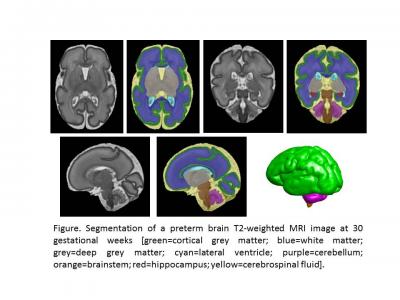

"Compared with macronutrients like carbohydrates and proteins, lipid intake during the first month of life is associated with increased overall and regional brain volume for micro-preemies," says Catherine Limperopoulos, Ph.D., director of MRI Research of the Developing Brain at Children's National and senior author. "Using non-invasive magnetic resonance imaging, we see increased volume in the cerebellum by 2 weeks of age. And at four weeks of life, lipids increase total brain volume and boost regional brain volume in the cerebellum, amygdala-hippocampus and brainstem."

The cerebellum is involved in virtually all physical movement and enables coordination and balance. The amygdala processes and stores short-term memories. The hippocampus manages emotion and mood. And the brainstem acts like a router, passing messages from the brain to the rest of the body, as well as enabling essential functions like breathing, a steady heart rate and swallowing.